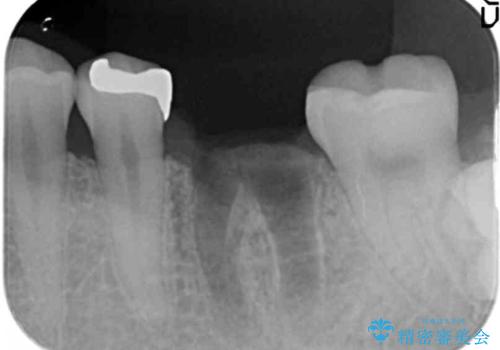

- 44万円(インプラント・チタンカスタムアバットメント・ジルコニアクラウン・仮歯)費用は治療当時の料金となります

抜歯後、骨の再生を待ったことで、清掃性の高い位置に埋入を行い機能的・審美的なインプラント治療を行うことができました。